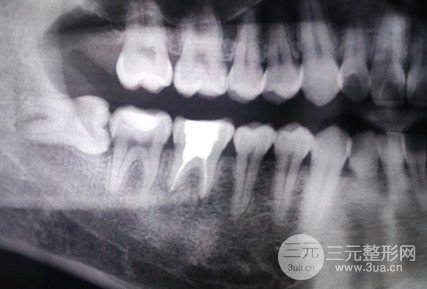

根管缓解

根管填充是对于牙髓炎或死髓牙、根尖疾病无法留下活髓的破损牙,开展缓解的合理方法。根管填充后立即戴冠,这种提议是以有益于求美者的视角确立的!从临床医学视角来说,戴冠修复也是根管填充的必需流程!因此,做了根管填充的小伙伴们!一定要遵医嘱,立即戴上牙冠,这才算是对自己牙齿健康负责的行为!

根管后做牙冠的必要性

1、根管填充是以药品及其器材的应用来将根管中的杂质及其病菌竭尽所能地清理杀菌干净。不过,这样的杀菌过程假如要用心的开展,却必须去祛除不少被细菌感染的牙齿,以及迫不得已修整的牙体结构。因此绝大多数的牙齿要是开展根管填充,则可能不太足以支撑咬合的力量而可能破裂,纯粹用材料已经不能恢复作用,就算能恢复*作用也不好。

2、经过根管填充后的牙齿丧失了来源于牙髓的养分供给,就像丧失根茎的树木一样,渐渐地枯萎变的很敏感,导致牙齿的脆化增加,易破裂。

3、因为需要开展根管填充的牙齿通常已是龋坏(蛀牙)、缺失很大,这时尽管根管填充结束,不过其剩余的牙体结构是很敏感的,极其容易断裂、裂开,丧失常规的作用,纯粹用材料已经不能恢复作用。